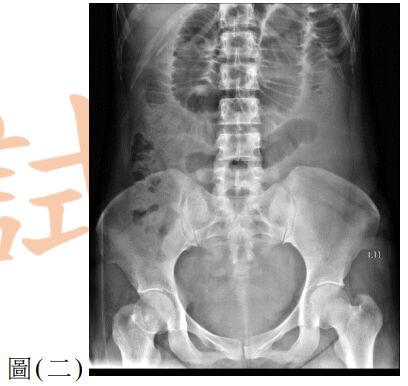

12. 一位 25歲男性因呼吸困難至急診就醫,主訴2天前工作撞擊到右側胸部,胸部X光檢查如圖(三),下列處置何者較適當?

(A) 立即給予右側胸管置入引流 (B) 觀察呼吸困難狀況並給予肌肉鬆弛劑 (C) 立即安排胸腔鏡手術治療 (D) 安排胸部電腦斷層檢查確立診斷